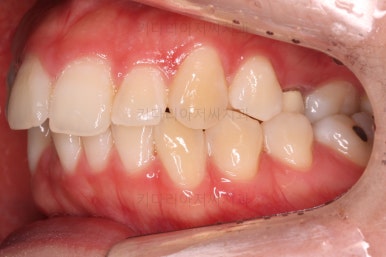

여전히 돌출감이 있기 때문에 전 치열을 후방이동해서 입매를 개선해 주고요.

앞에서 봤을 때 치열은 가지런해졌지만 기울어진 느낌을 조금이라도 잡아보고자 미니스크류를 이용해서 입매 개선 및 기울기 개선을 시도했습니다.

미니스크류가 구성되었고요.

기울기와 돌출입을 개선하고자 이러저리 밀고당고 하는 모습입니다.

오히려 이전 사진보다 치열이 더 틀어지고 잘 안맞는 모습이죠?

환자분도 이때부터는 매우 힘들어하시긴 합니다.

괜히 잘 맞아보이는 걸 손대서 이상해지는 느낌일거거든요.

잘 설명 드려가면서 좀 더 좀 더 진행해 봅니다.